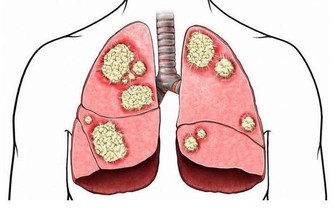

酒精容易引起酒精性肝炎、肝纖維化、肝硬化等情形,

而肝癌也是我國常見的惡性腫瘤之一,常見於中年男性。

因其惡性度高、病情進展快,病人早期一般沒有什麼不適,

一旦出現症狀就診,往往已屬中晚期。